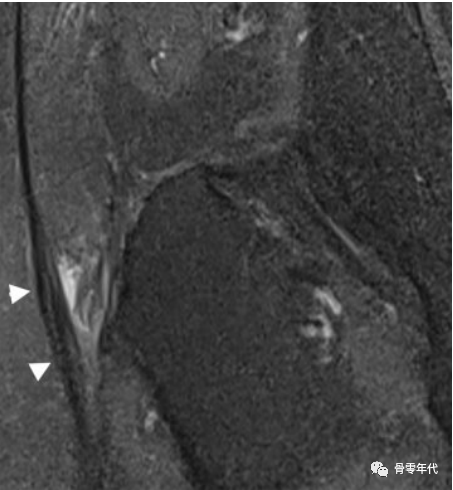

手术后病理

高达20%的THA术后患者可能会出现外展肌腱功能不全,这主要取决于所选择的手术入路。四种经典的手术入路是直接前入路、前外侧入路、外侧入路(也称为经臀肌入路)和后路入路。前侧和前外侧入路为肌间入路,试图减少软组织损伤。在外侧入路中,臀中肌腱必须被切开并分离;在后路手术中,短外旋肌必须分离,然后再固定。

在T1加权像上,一位79岁的男性,在全髋关节置换术的后路手术后,有明显的短外旋肌腱病变。(a)梨状肌腱变薄(黑色箭头),闭孔外肌腱变粗和磨损(虚线箭头)。(b)闭孔内肌腱撕裂和回缩,肌肉严重萎缩(箭头)。